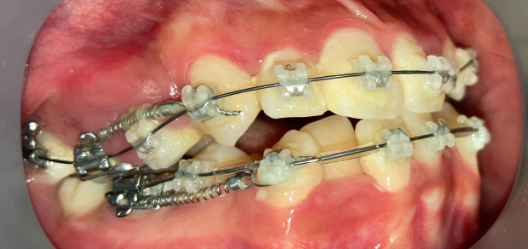

インプラントアンカー装着中の矯正治療経過|奈良の矯正歯科

アンカー装着中

インプラントアンカーで上の歯列全体を後方に移動。抜歯せずにガタガタと口元の突出感を改善しました。